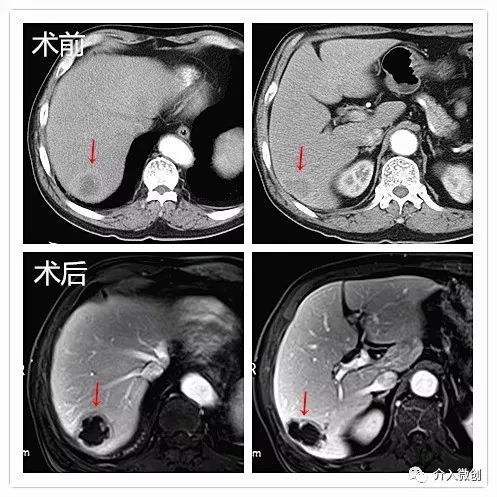

老年男性,诊断为右肺癌并纵隔淋巴结、肝多发转移。活检病理示:大细胞性未分化癌。肺部病灶经姑息性放化疗后有所控制,但肝脏病灶出现进展,遂行载药微球栓塞治疗。

肝动脉化疗栓塞治疗

复查MRI显示病灶大部分坏死

复查PET-CT亦提示病灶大部分已无活性,仅病灶下缘残存少许活性,后续行局部放射性粒子植入控制